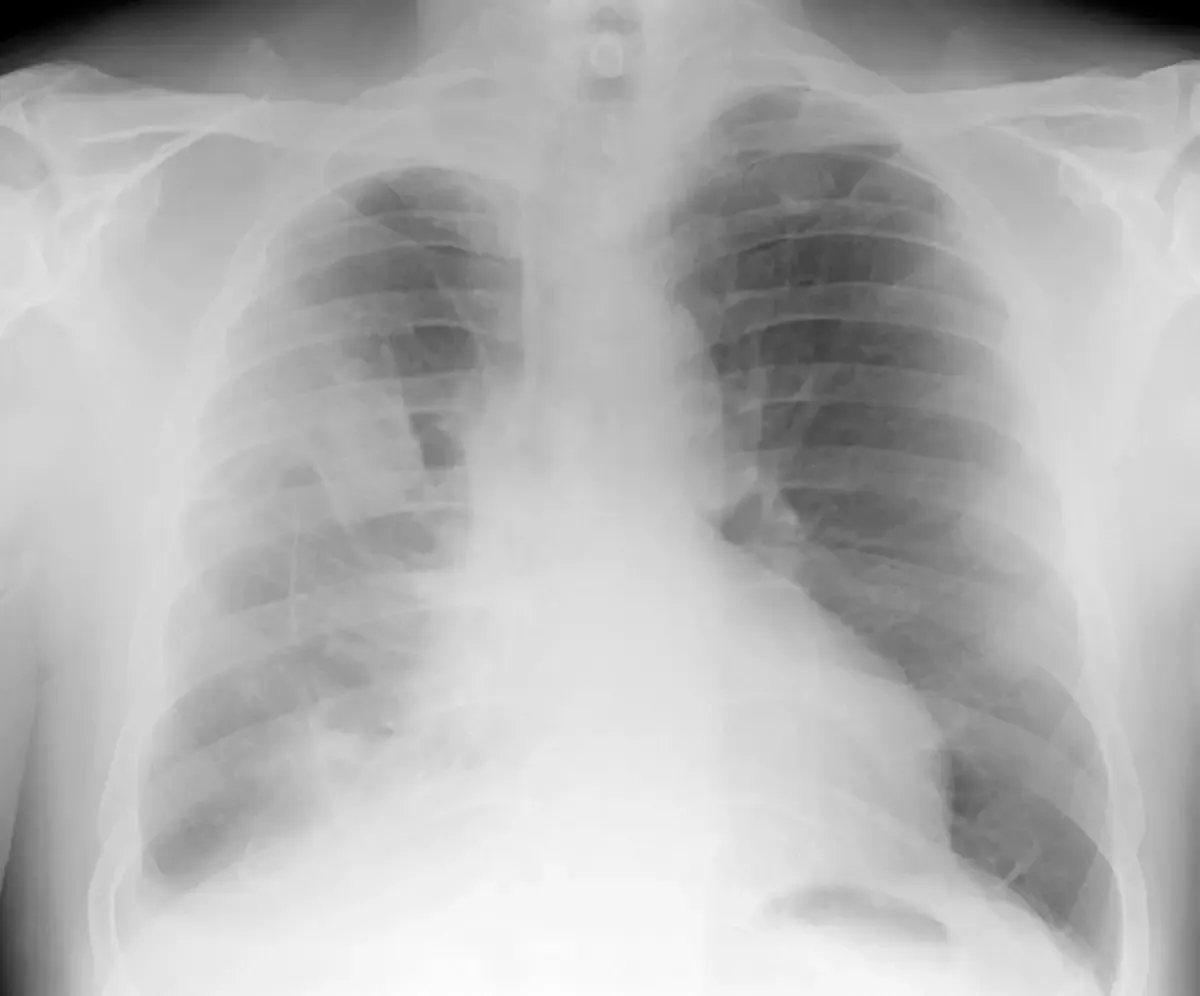

The GP will likely organise Xray's and/or a CT scan and blood tests. If there is a collection of fluid, further investigation may be required and drainage of the fluid carried out where a sample of fluid is sent to pathology for testing.

Sometimes a diagnosis is not able to be made from the pleural fluid. In this case a cardiothoracic surgeon will perform a pleural biopsy where a sample is taken and examined under a microscope.